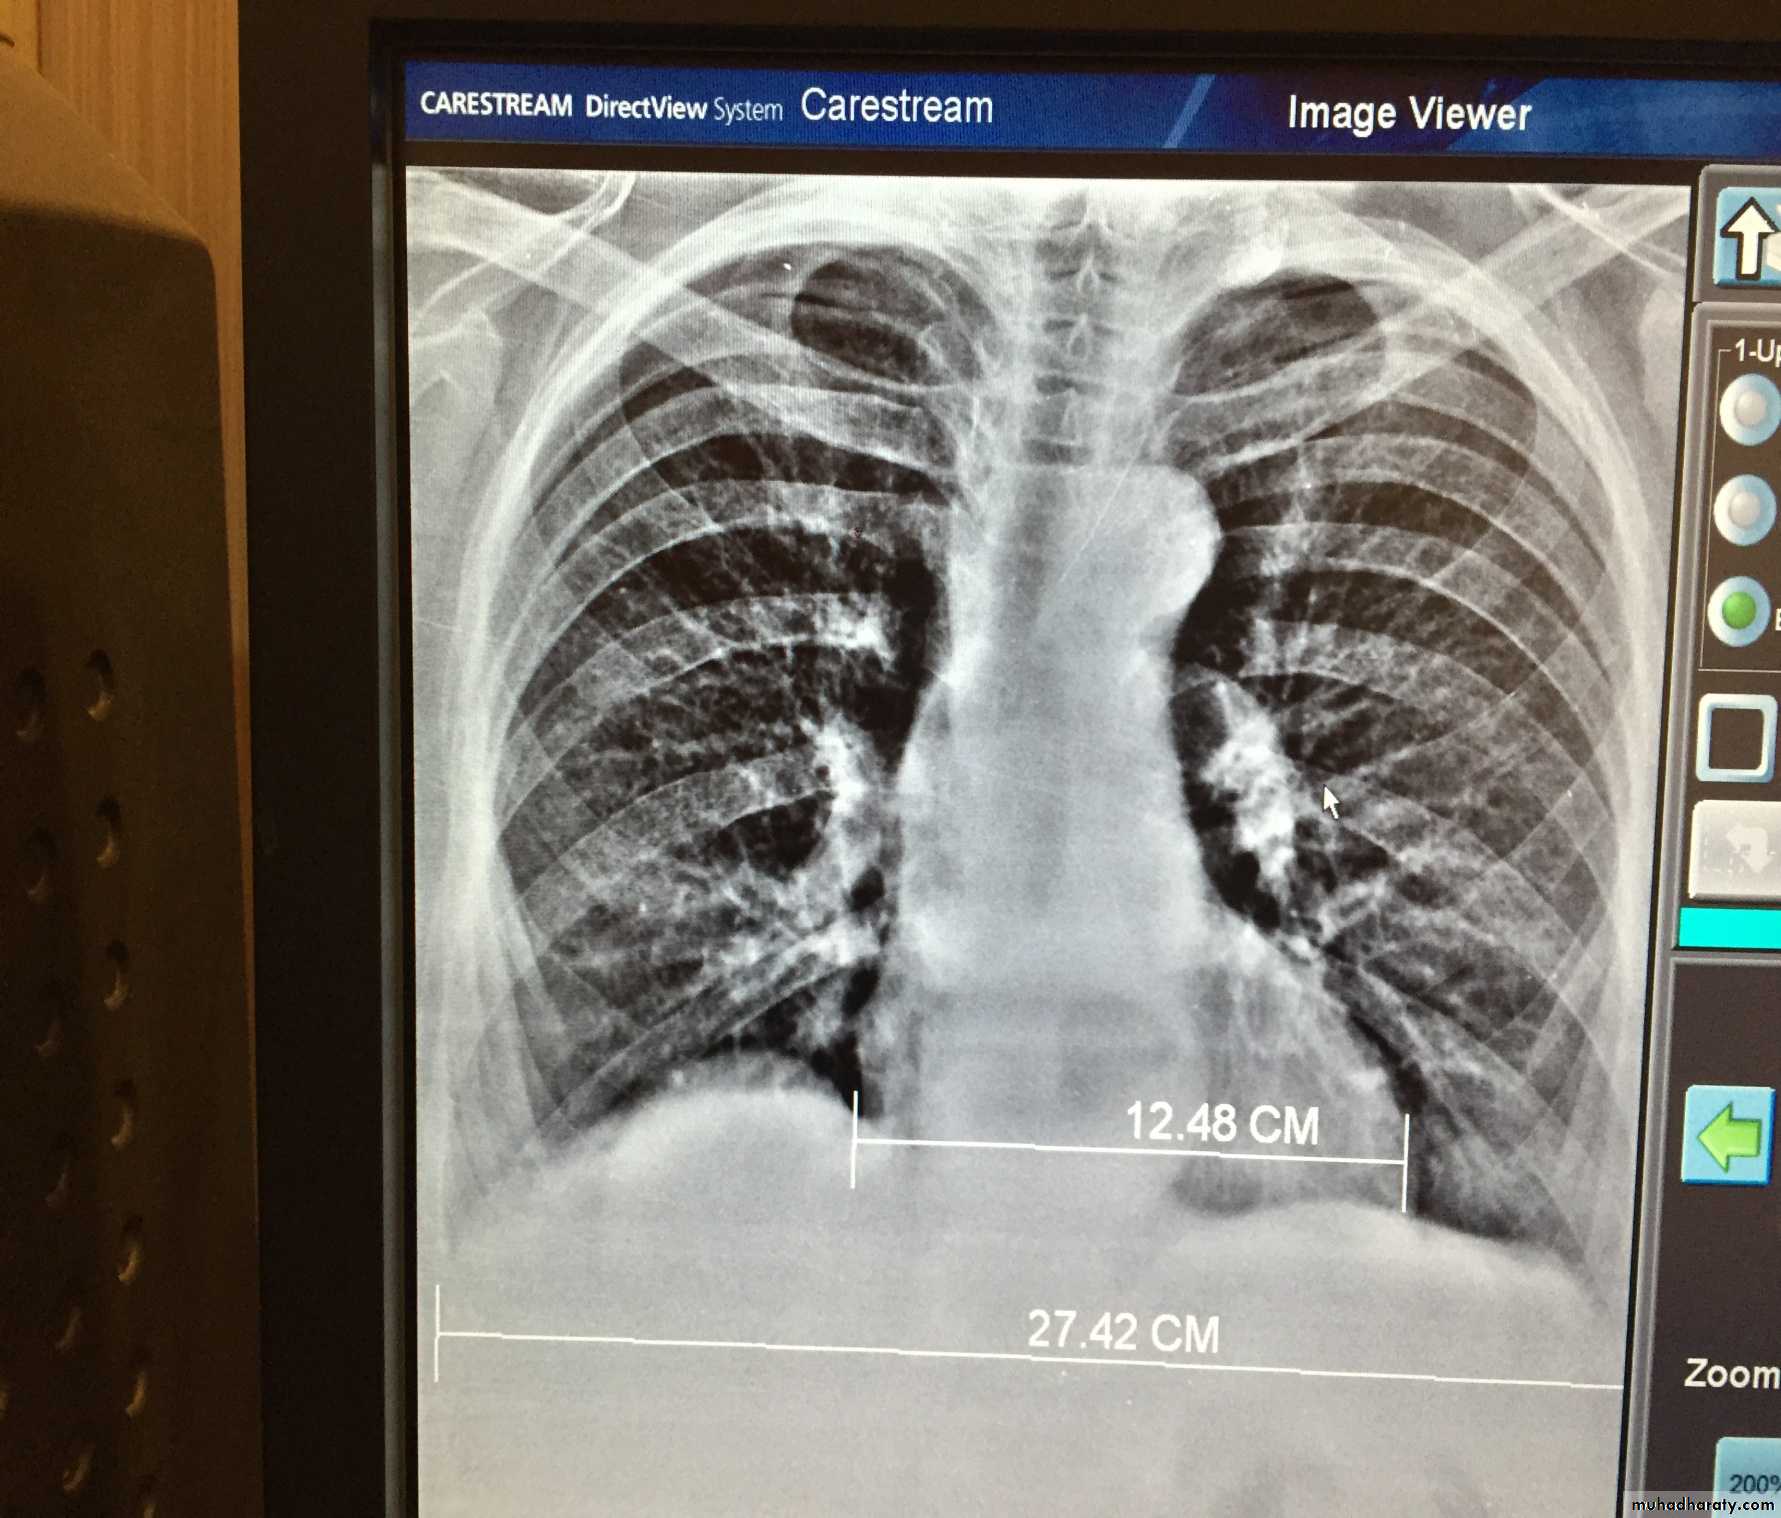

The pleura :

• Pleural effusion : collection of fluid within the pleural space. This can be further divided into Transudate , exudate, according to protein content .Other type of fluid collection within pleural space are

empyema (pyothorax)

chylothorax (lymph in pleural space )

haemothorax

• Chest x-rays are the most commonly used examination to assess for presence of a pleural effusion, however it should be noted that on a routine erect frontal chest x-ray as much as 200-500 ml of fluid is

• required before it becomes evident .

blunting of the costophrenic angle

blunting of the cardiophrenic angle

fluid within the horizontal or oblique fissures

eventually a meniscus will be seen, on frontal films seen laterally and gently sloping medially

with large volume effusions, mediastinal shift occurs away from the effusion

Pleura effusion signs

Obliteration of costo-pherinic anglesMeniscus sign

Lenticular sign